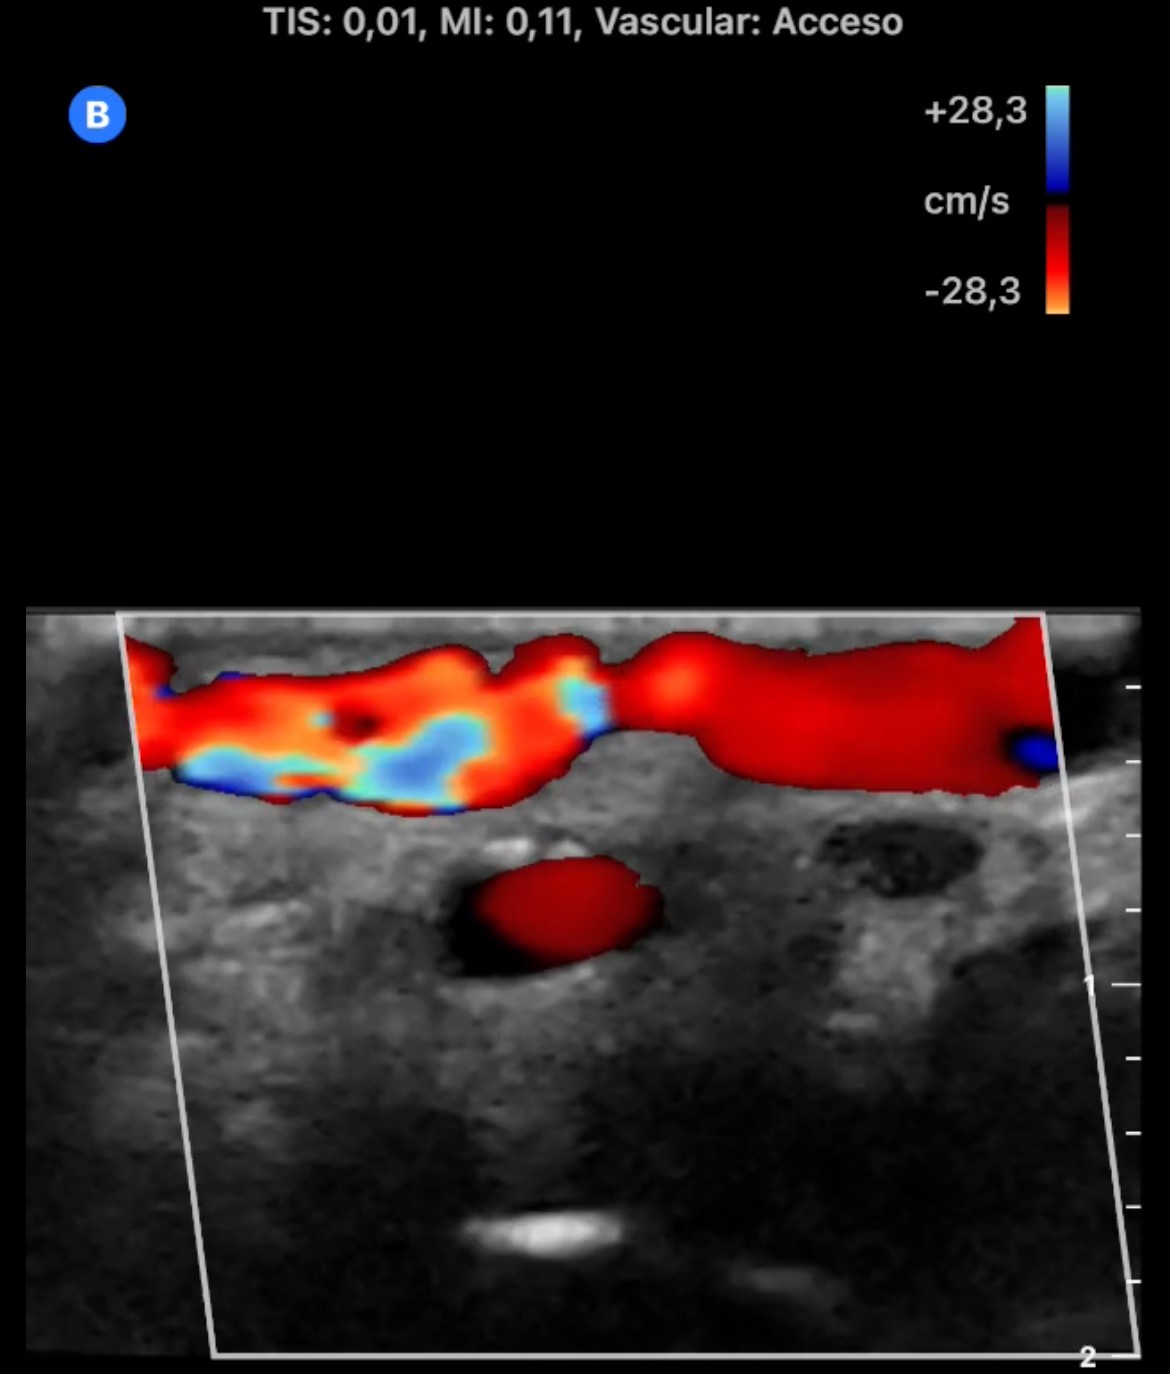

En la cara palmar de la muñeca derecha se aprecia un aumento de tamaño de las venas superficiales con flujo Doppler color en su interior. En arteria radial se observa flujo muy turbulento con comunicación de arteria radial con una vena superficial del antebrazo.